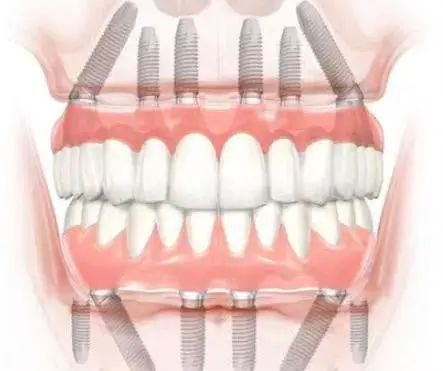

C. 设计细节:微螺纹与锥形连接

它的设计考虑到了东方人牙槽骨相对偏窄、偏软的特点。顶部的微螺纹设计能有效分散咬合压力,防止骨吸收(也就是防止牙龈萎缩导致植体暴露),这对于延长植体寿命至关重要。

多颗/全口缺失的老年人:全口种牙动辄十几颗,选八维能比选欧美品牌省下一辆小轿车的钱,且功能上几乎无差。